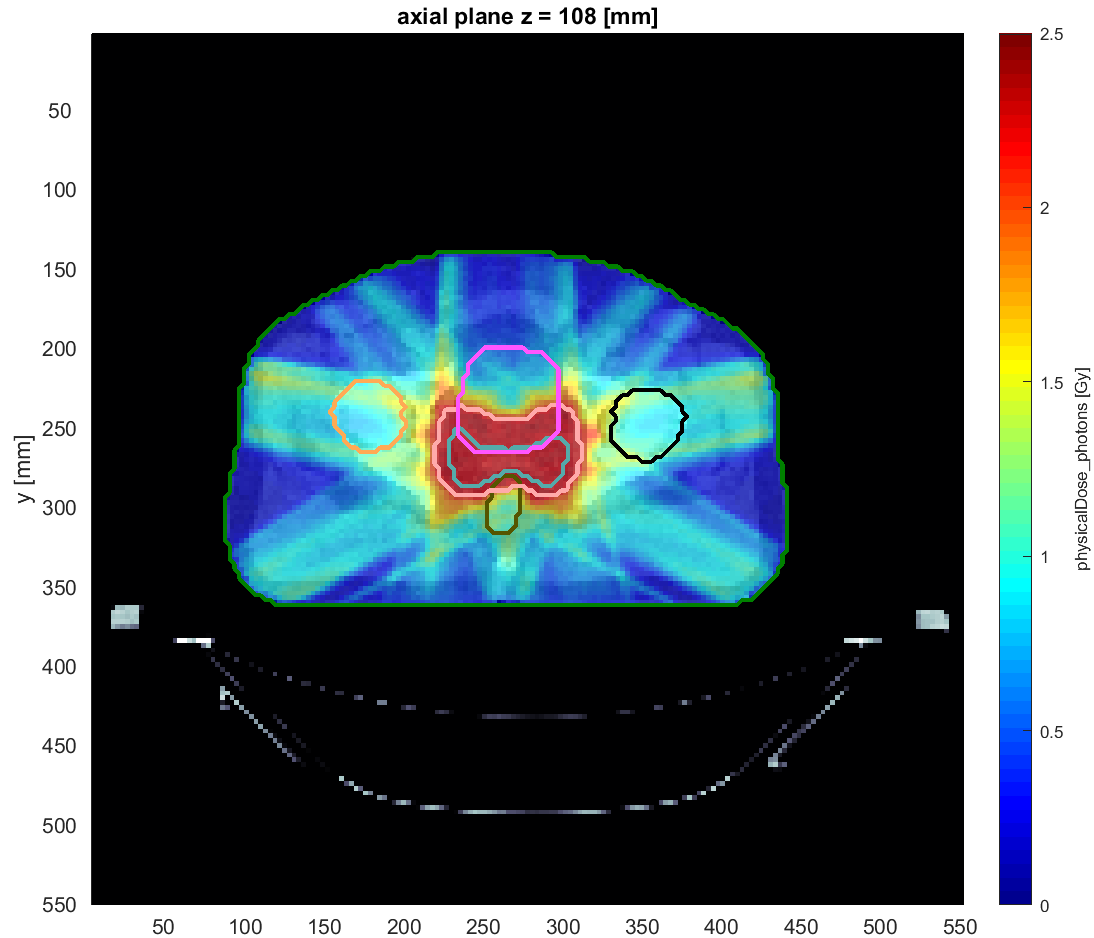

They have developed the matRad open source Treatment Planning System which is the basis for the Particle Therapy MasterClass education project.

Έχουν αναπτύξει το Σύστημα Σχεδιασμού Θεραπείας ανοιχτού κώδικα matRad , το οποίο αποτελεί τη βάση για το εκπαιδευτικό έργο Particle Therapy MasterClass για τη θεραπεία σωματιδίων.